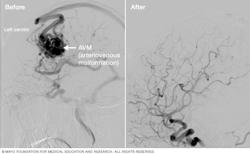

Brain AVM before and after Gamma Knife treatment

Brain arteriovenous malformation before Gamma Knife treatment (left) and 52 months after the procedure (right)

- Brain arteriovenous malformation (AVM). An AVM is a tangle of blood vessels that creates irregular connections between arteries and veins in the brain. Untreated, it can cause a stroke or bleeding in the brain. SRS causes the blood vessels to close off over time, lowering the risk of bleeding.

- Brain AVM blood vessels thicken and close off in 1 to 3 years.